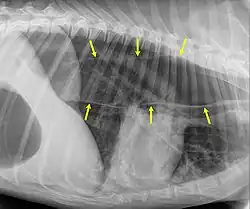

Der Verdacht auf Megaösophagus ergibt sich aus der Anamnese und dem klinischen Bild. Wird Druck auf den Bauch ausgeübt, kann sich die Speiseröhre im Hals sichtbar aufblähen. Eine Röntgenaufnahme des Brustkorbs zeigt eine geweitete, mit Luft und/oder Futter gefüllte Speiseröhre. Bei angeborenem oder erworbenem Megaösophagus ist die Weitung meist gleichmäßig; bei Megaösophagus als Folge eines persistierenden rechten Aortenbogens oder einer anderen Striktur ist die Speiseröhre nur vor der Engstelle aufgeweitet.[5]